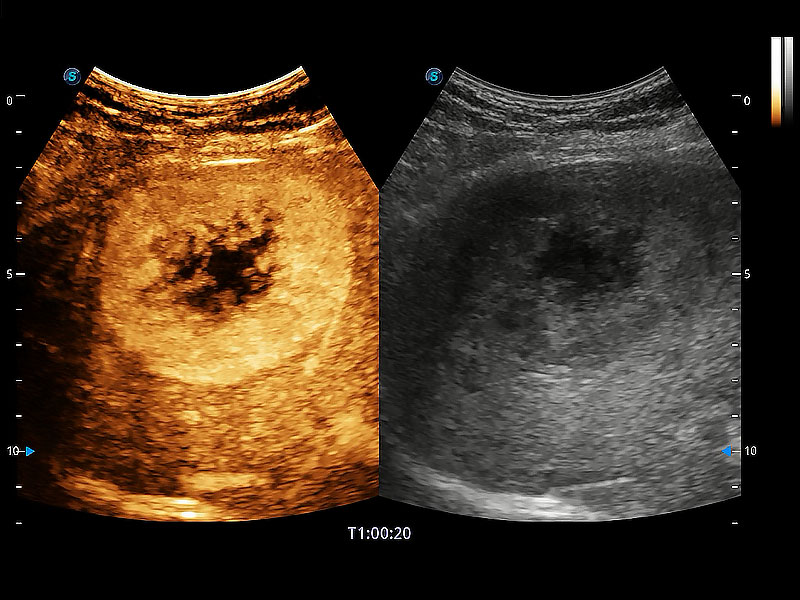

• Bright Flow 立体血流成像

在传统二维血流成像的基础上,呈现血流的立体感,具有动感的生命力之美。即便是微小的血管也能轻松应对,提高了血流的视觉敏感性。

(犬)肝脏

(犬)胎儿主动脉弓立体血流